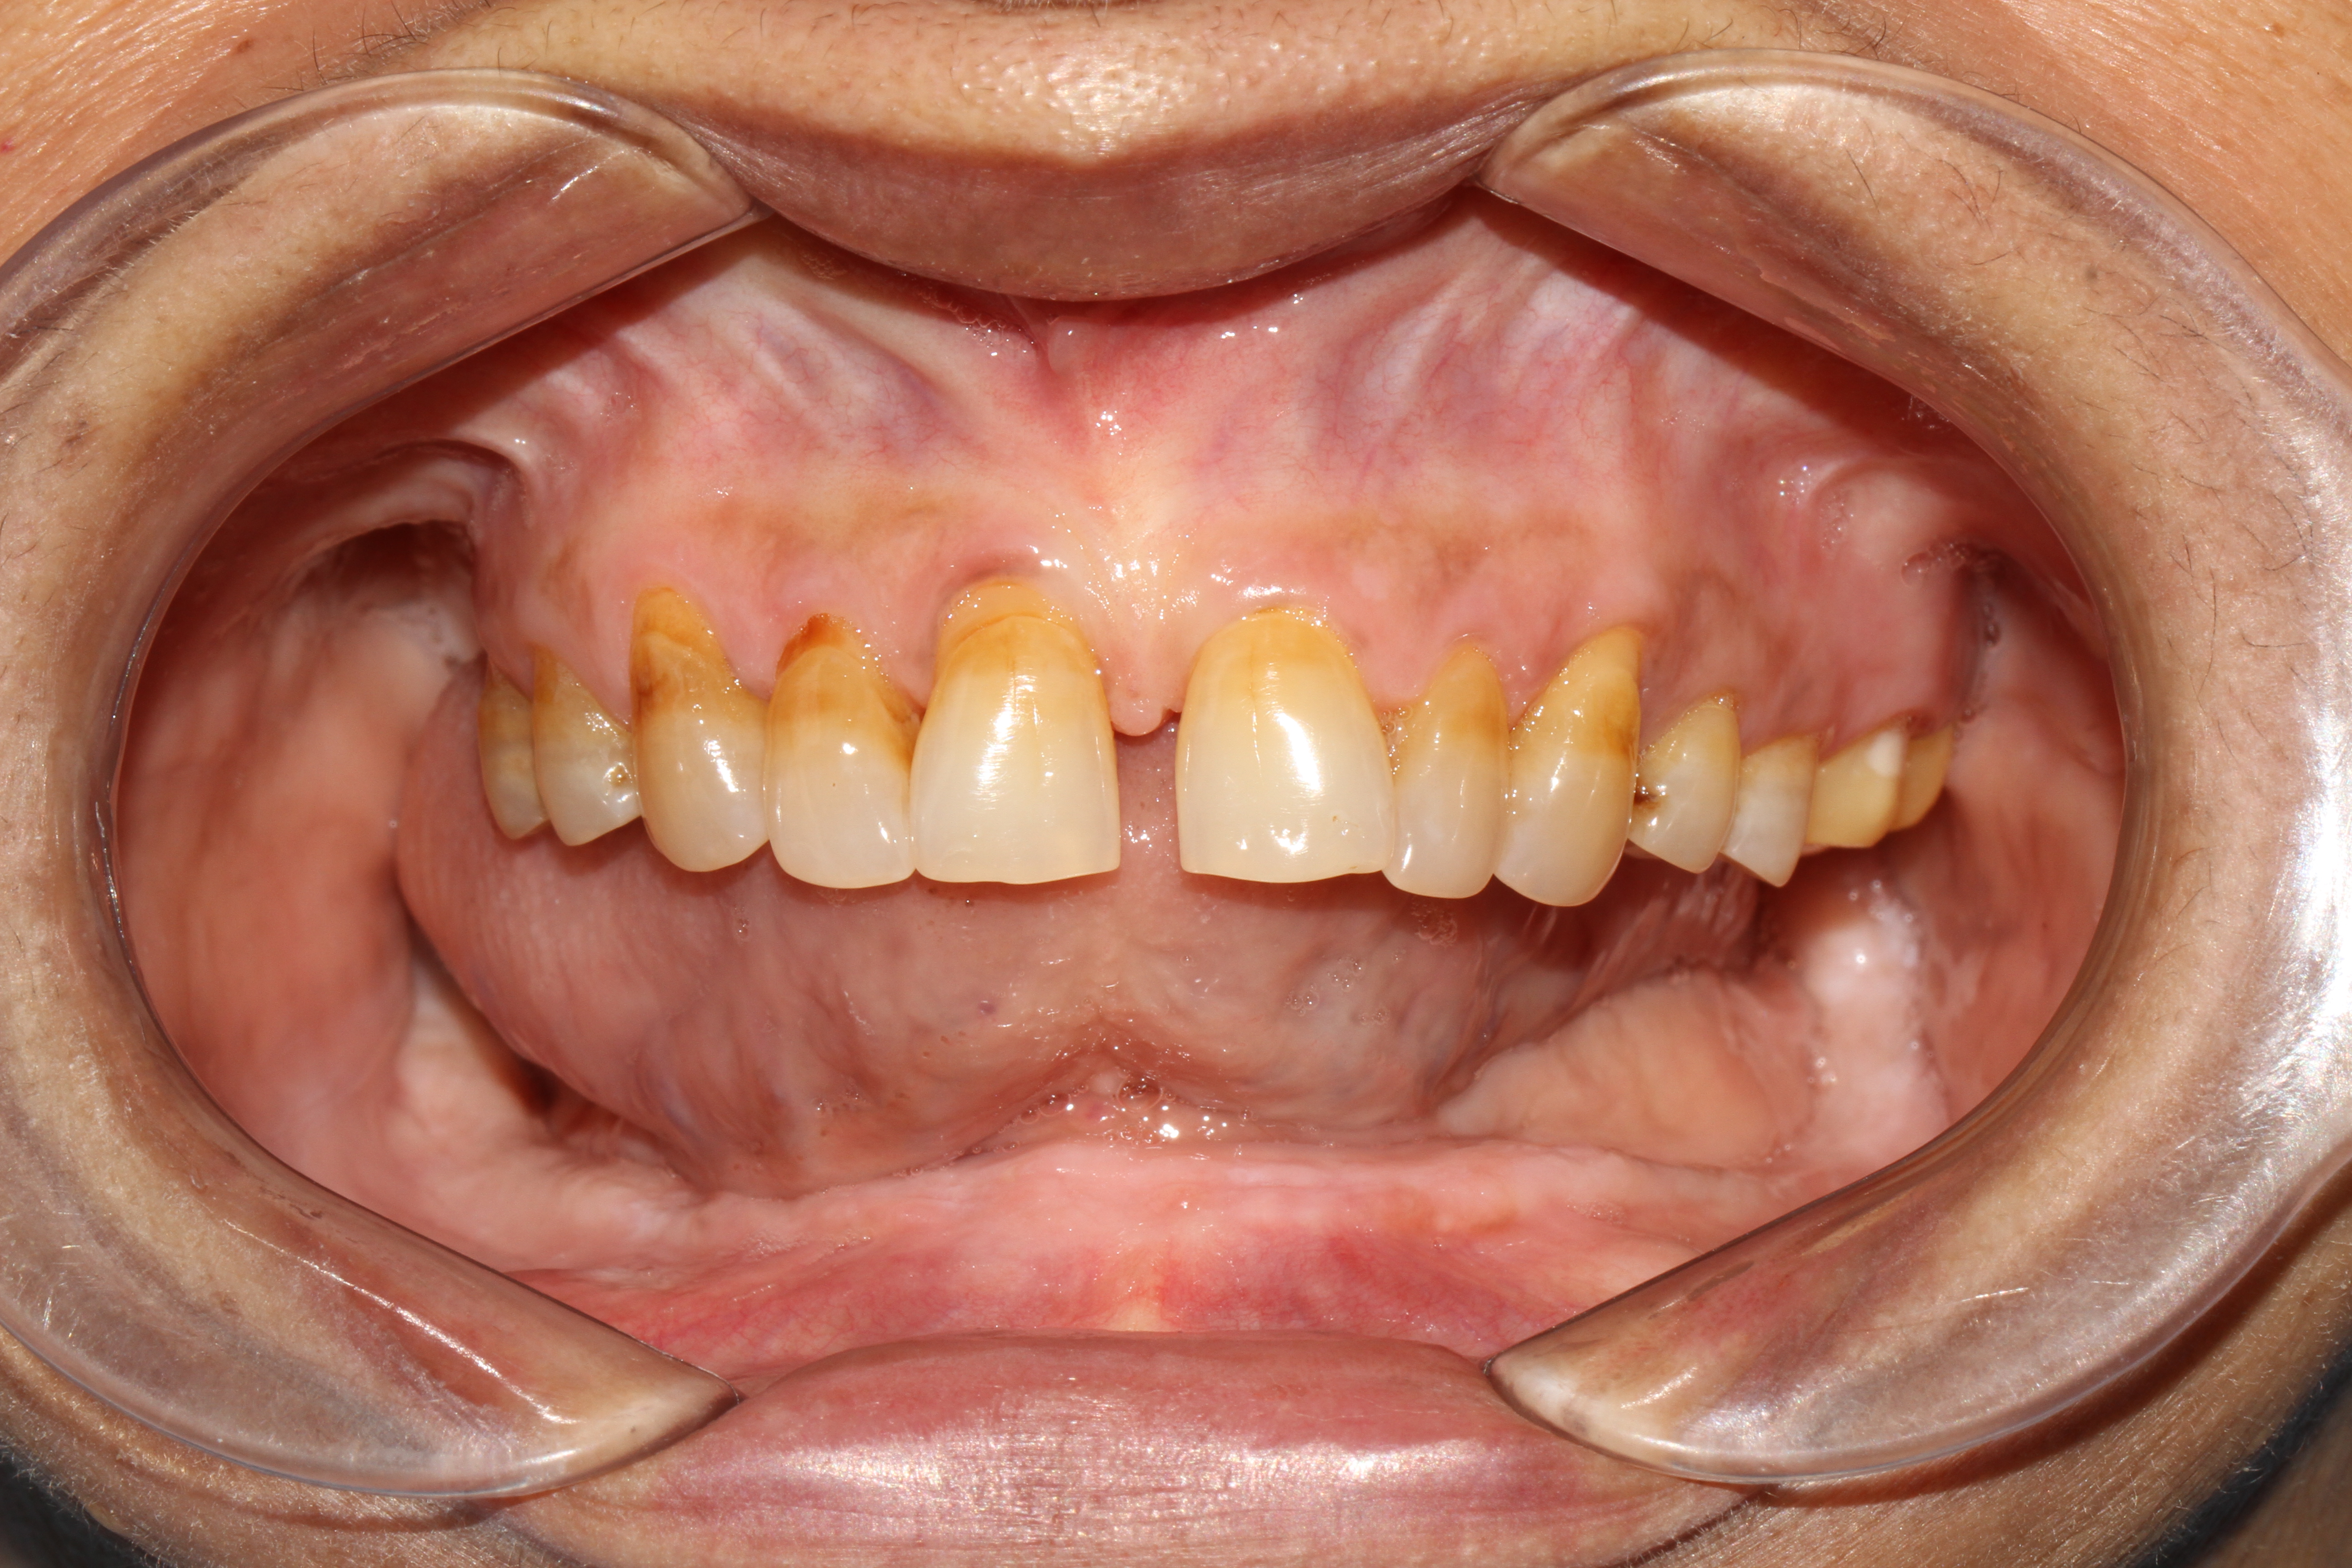

When it comes to replacing the entire arch of a lower jaw with 14 teeth, options like replacement with a zirconia crown, which is free of metal or porcelain fused to metal (ceramic) crown can be used. These crowns are fabricated in our hi-tech lab in 3 days which is fixed with the new generation of immediate loadable single piece implant. At Jani's Implant Cantre and Smile Studio, basal implants with a combination of crestal implants are used. Using this art of implant placement all 14 teeth which include the second molars are replaced. The introduction of second molars by this step will help the patient chew in a more efficient way similar to that of natural teeth. depending upon the patient's medical status, oral health and the quality of the bone, 6-8 implants are placed on which 14 teeth (full arch) is fixed. This is a full mouth immediate loadable implant therapy for the lower jaw. This is done in the form of permanent teeth in 3 days protocol where no bone augmentation and bone grafting is needed.

Removable implant-supported dentures also known as snap-on dentures are godsend options to patients who desire an economical solution to loose dentures. In this particular procedure, the denture for the lower jaw is connected to a ball or a bar attachment, which in turn is anchored on two or more mini dental implants in the front part of the lower jaw. Even though this can be done and is more economical, the success rate of fixed teeth in 3 days is much higher and therefore more recommendable.